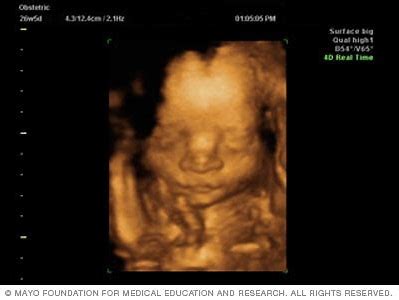

6. He it is Who shapes you in the wombs as He pleases. There is no god but He, the Exalted in Might, the Wise.